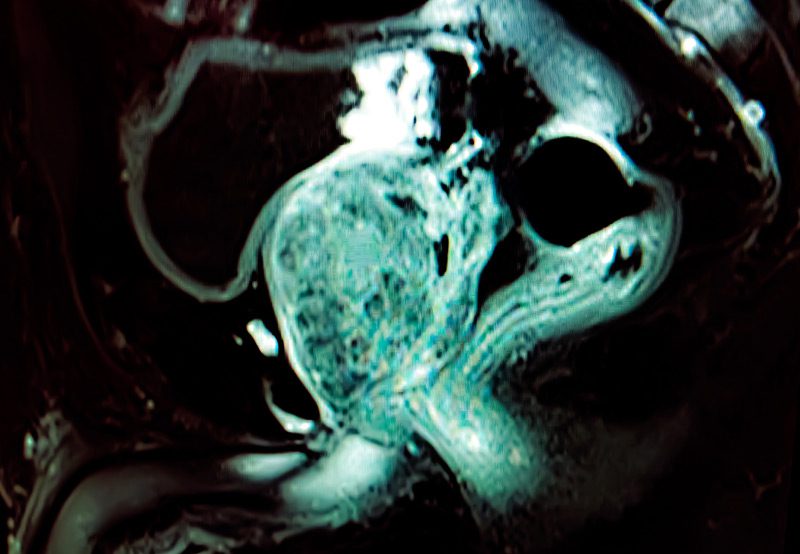

MRI-scan-showing-prostate-gland-imaging

• MRI or Ultrasound Imaging: Used to identify suspicious areas within the prostate.